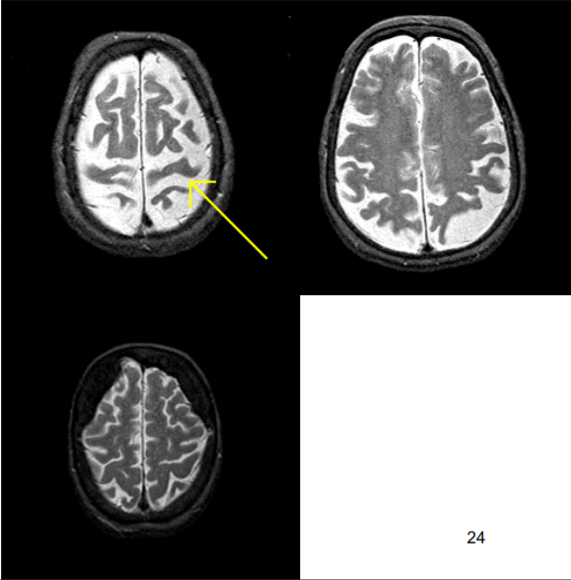

What can be seen in this scan?

[EXTRA? Possible MCQ]